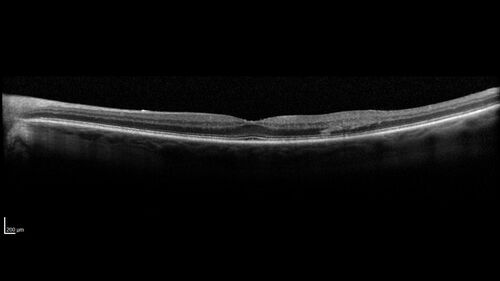

BRVO with good vision

87 year old man with good vision (diabetes without retinopathy). VA 20/25 OU. Vision never worsened from BRVO OS.